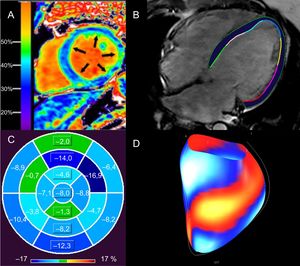

La miocardiopatía dilatada (MCD) se caracteriza por dilatación y disfunción del VI o de ambos ventrículos que no se explican por condiciones de sobrecarga hemodinámica o la enfermedad coronaria33. Se han identificado multitud de etiologías genéticas y ambientales, además de más de 50 genes patógenos33. La fibrosis (tanto focal como difusa) causa reentrada relacionada con la cicatriz y AV34-37. El riesgo de AV y MSC relacionado con el RTG se ha documentado ampliamente en este grupo heterogéneo de pacientes (tabla 2)9,24,34,35,38-46. Se han descrito varios patrones de RTG distintos, con algunos estudios que correlacionan el RTG de la pared media con un riesgo mayor, aunque este hallazgo no fue tan claro en otros estudios (tabla 2)35,41,43,44,47,48. En determinadas MCD genéticas, se han podido observar las implicaciones pronósticas del RTG para la AV/MSC; por ejemplo, mutaciones de la lamina A/C y distrofia muscular de Duchenne y Becker49,50. Según varios estudios, cada vez hay más indicios pronósticos de la presencia y la extensión del RTG en la «miocardiopatía no isquémica», que se superpone a la MCD36,38,48,51,52. También se observó que el FVE es un predictor independiente de una variable combinada (incluida la AV) en la MCD no isquémica (figura 2A)12,53. En la distrofia muscular de Becker, el aumento de la FVE se ha relacionado con AV (odds ratio [OR]=1,97; IC95%, 1,21-32,22; p=0,032)54. La alteración del strain longitudinal global del VI (HR=1,27; IC95%, 1,06-1,52; p <0,02), evaluada por medio de feature tracking, se relacionó de modo independiente con una variable combinada que incluía AV y MSC en un estudio con 210 pacientes con MCD (figuras 2B-D)22.

Evaluación de la fibrosis miocárdica difusa y consecuencias funcionales con resonancia magnética cardiaca de pacientes con MCD. A: elevación de la FVE del 37% en un paciente con MCD no isquémica; una FVE alta se relaciona con arritmias ventriculares en la MCD no isquémica12. B: contornos epicárdicos y endocárdicos del VI en una imagen de precesión libre en estado estacionario, horizontal y de eje largo, de un paciente con MCD idiopática (FEVI <10%) a partir de la cual se calcula el strain longitudinal global con rastreo de características. C: mapa polar del strain longitudinal segmentario del VI en el paciente (B), que muestra alteración del strain longitudinal global (–4,4%); los segmentos del ventrículo izquierdo se señalan con distintas tonalidades de azul (los tonos más oscuros indican mejor strain segmentario) y verde (peor strain segmentario); el strain longitudinal global superior al –12,5% se relaciona con muerte súbita cardiaca en la MCD no isquémica, independientemente de la FEVI22. D: visualización de la superficie del strain segmentario del VI de (B), con segmentos azul/blanco que representan el mejor strain respecto a los segmentos rojo/amarillo (peor strain). FEVI: fracción de eyección del ventrículo izquierdo; FVE: fracción del volumen extracelular; MCD: miocardiopatía dilatada; VI: ventrículo izquierdo. La imagen A se ha reproducido con autorización de Schelbert et al.53. Esta figura se muestra a todo color solo en la versión electrónica del artículo.